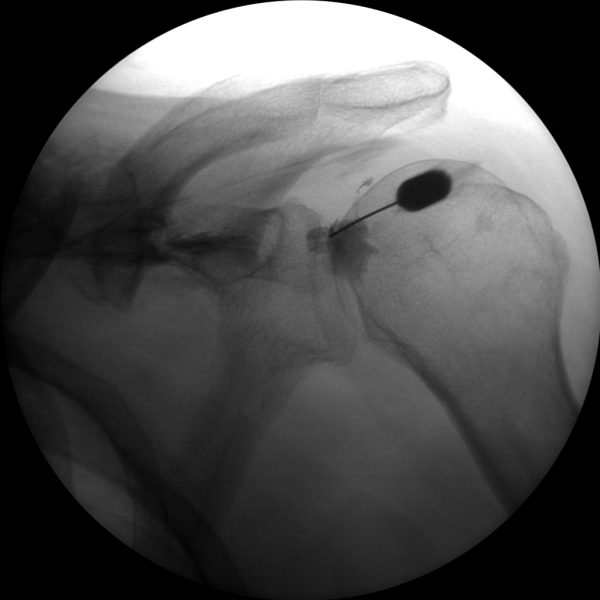

Joint Injections

Skan-C proves highly effective in performing joint injections, a procedure commonly used to administer pain-relieving medication directly into the affected joints, such as the knee, shoulder, or hip.